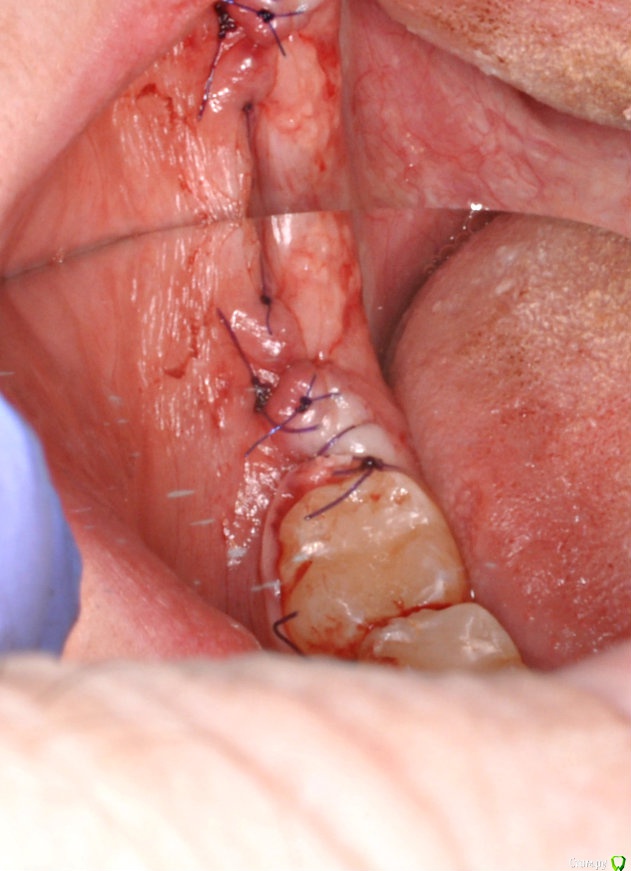

колесников Опубликовано 1 апреля, 2017 Автор Поделиться Опубликовано 1 апреля, 2017 Из свежего Ссылка на комментарий

колесников Опубликовано 2 апреля, 2017 Автор Поделиться Опубликовано 2 апреля, 2017 Тройной лоскут , вид через 5 -7дней. Снимок "до". И благодарность за скорое заживление 6 Ссылка на комментарий